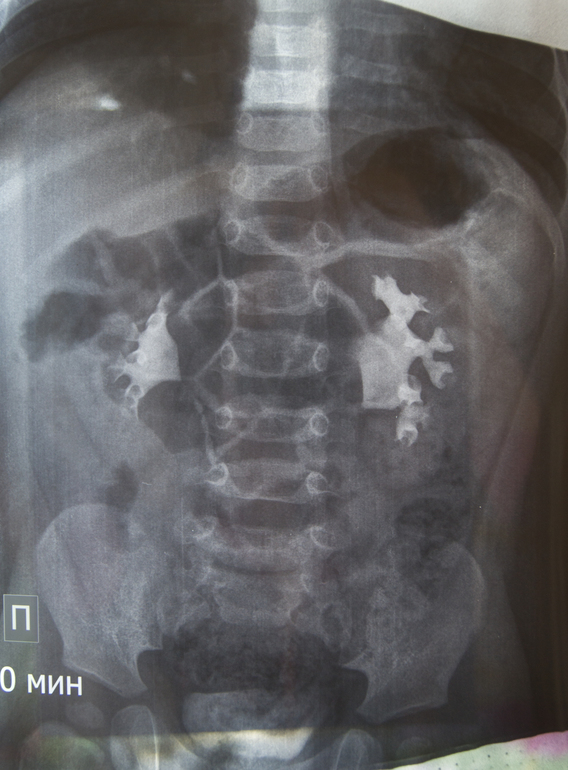

Ситуация 1: ребенку 1 год и 3 мес, в год прошли обследование (в/в уро- и цистография с контрастом), был поставлен диагноз "левосторонний гидронефроз 1 ст, фимоз". На апрель назначена операция по удалению крайней плоти. Нефролог говорит, что пока основной причиной гидронефроза признается именно фимоз. Дополнительных исследований (например, доплерография сосудов почек) не назначалось. Мой вопрос заключается в том, как часто (если таковое вообще возможно) фимоз может стать исключительной причиной гидронефроза? Если дело только в нем, операция окажется оправданной, если же препятствие в другом месте, ребенку предстоят "лишние" испытания, ведь вероятность того, что физиологический фимоз пройдет сам, высока. Для полноты картины я могу предоставить оцифровку рентгеновских снимков и выписку из истории болезни.

Если возможно, не могли бы Вы оценить результаты рентгенографического обследования моего младшего сына? На сколько качественно, на Ваш взгляд, были сделаны снимки? Согласно заключению нефролога, рефлюкс исключен. Если есть стриктура мочеточника (любой этиологии), должна ли она визуализироваться на рентгеновском снимке, или бывают случаи, которые проще диагностировать на УЗИ с диуретиком?

Я не берусь судить заочно, думаю слева нужно посмотреть на предмет абберантного сосуда в проекции пиело-уретрального сегмента